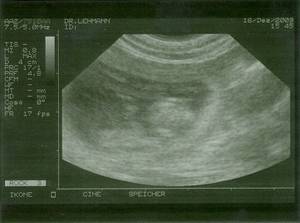

Und da so Allüren wie "mag Morgens kein Futter", "mir ist sooo schlecht", "hab Hunger auf ALLES" usw. auch schon da sind, können wir wohl als sicher annehmen: Angelina ist werdende Mutter! Erste Bilder von den Mini´s![]() ![]() Ich war bisher zwar noch nie, aber diesmal wegen der vielen Fragen war auch ich mit Angelina bei der Ultraschall-Untersuchung. Nachdem der erste Versuch am Dienstag gleich bei Eintritt in die Ordination des TA mit einem Knall, der den Ausfall des Gerätes signalisierte abgebrochen wurde, waren wir dann am Mittwoch, den 16. 12. andernorts erfolgreich.

Hier sind sie nun, die Bilder von Tag 29. Viel sieht man nicht, live war es schon spannender, mal hier ein Beinchen, mal hier eine Nase zu sehen - oder es sich zumindest einzubilden.

Auf den Bildern sieht man ja sowieso immer nur Einzelne oder maximal zwei, aber soweit Arzt und ich das sehen konnten sind es mindestens sechs Mini´s, die sich da auf die grosse weite Welt vorbereiten.